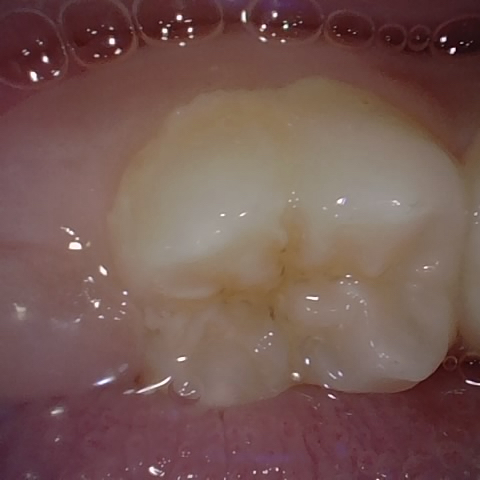

Annotated as "Good"